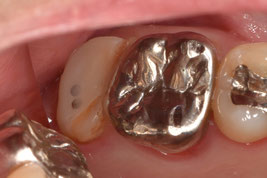

3週間後の経過観察で無事に生着していることを確認しました。歯肉の炎症も消失し、良好な経過と判断したため歯冠修復に移行しました。

近遠心的幅径を大幅に縮小させて、歯牙にかかる咬合力を軽減させると同時に、遠心部の清掃性を改善させました。